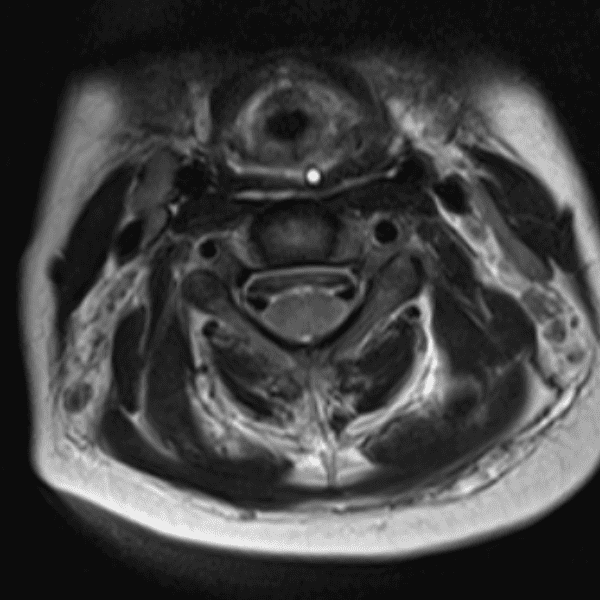

Simulates call by including subtle or difficult cases and some normals.

35 cases